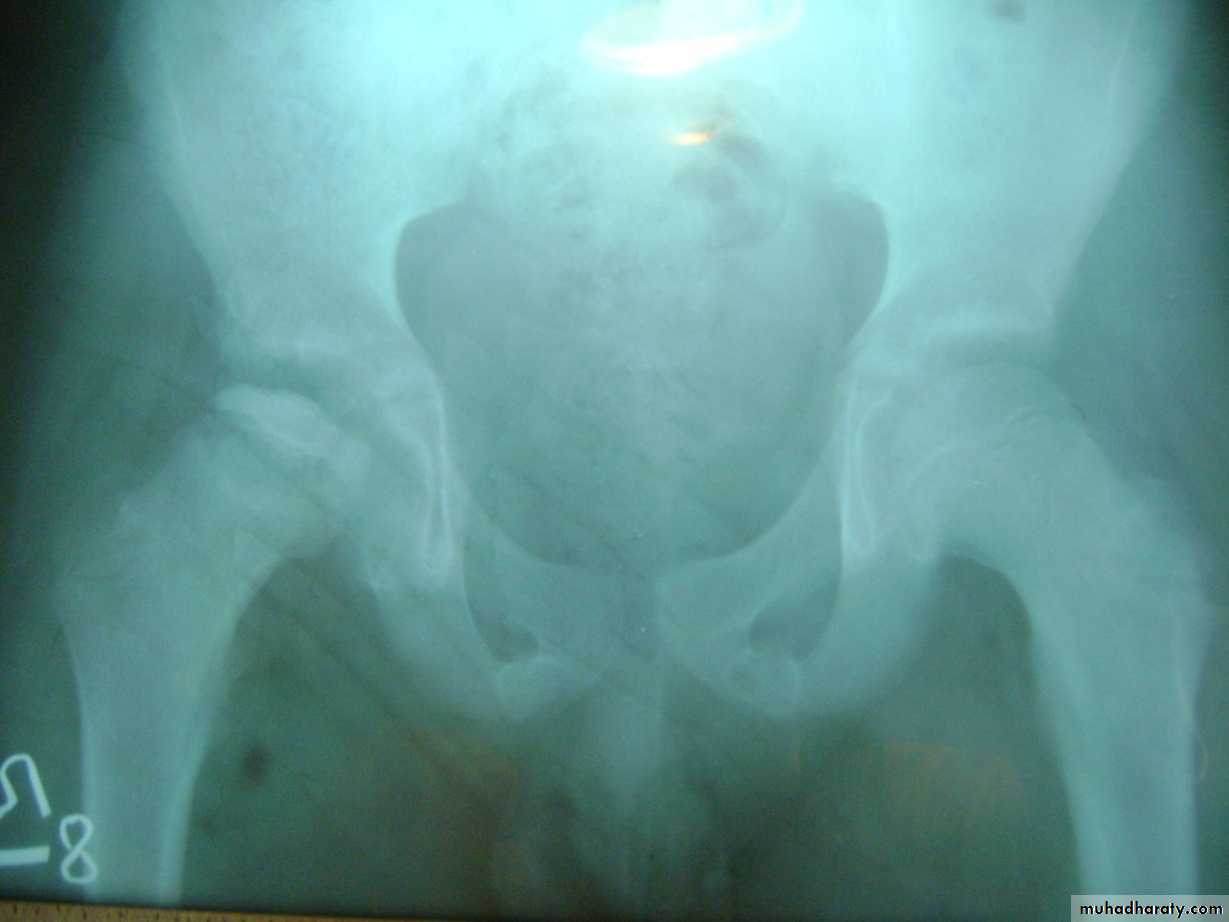

Slide 18. 1- comment on the xray2- the best response to you for urgent treatment